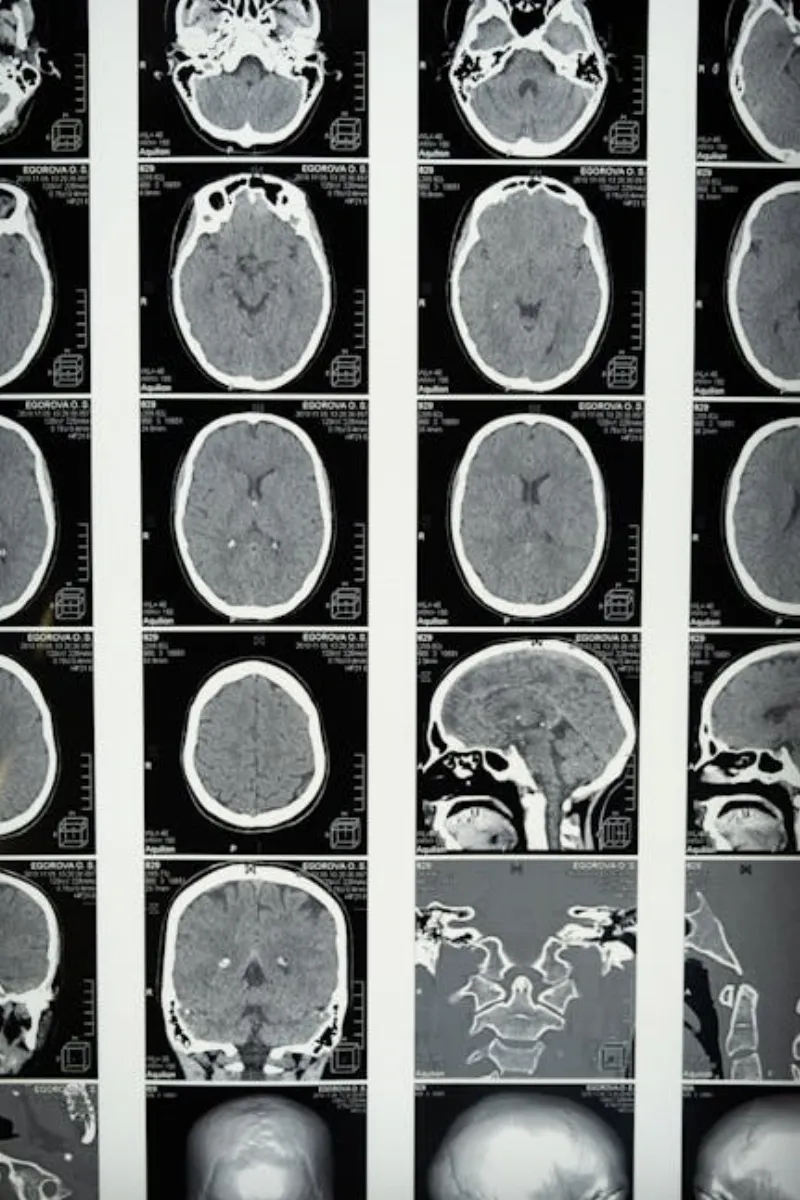

Selon une étude publiée dans le journal Nature Communications, les scans cérébraux montrent que les niveaux d'activité augmentent pendant les premières étapes du sommeil. En fait, certaines zones du cerveau impliquées dans le traitement des émotions et des souvenirs peuvent devenir encore plus actives lorsque nous dormons. C'est comme si nos cerveaux travaillaient en heures supplémentaires, trier les expériences de la journée et nous préparer pour demain.